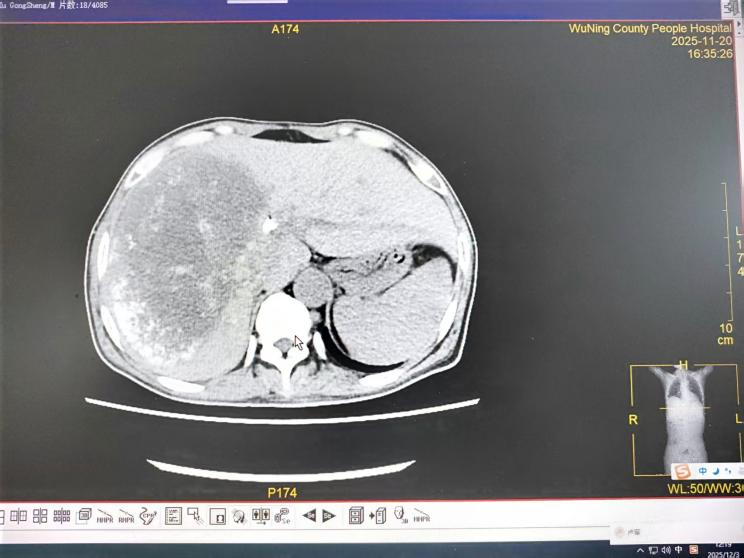

六、肿瘤科:介入综合,缓解晚期肿瘤之苦

对于已失去手术机会的晚期肝癌伴梗阻性黄疸患者,肿瘤科介入团队发挥了关键作用。一例直肠癌肝、肾上腺多发转移导致严重黄疸、肝功能受损的患者,情况危急。团队首先行“经皮胆管支架植入+引流术”,快速解除胆道梗阻,改善肝功能。待患者状况稳定后,又为其制定了序贯的“肝动脉灌注化疗联合栓塞术(HAIC+TACE)”方案。经过数次介入治疗,患者肝内转移灶明显缩小,黄疸完全消退,肿瘤标志物显著下降,生活质量得到极大改善。这凸显了我院在晚期肿瘤并发症处理及局部介入综合治疗方面的强大技术支撑。

2025年08月31日CT示:

2025年9月29日CT示:

2025年11月20日CT示: